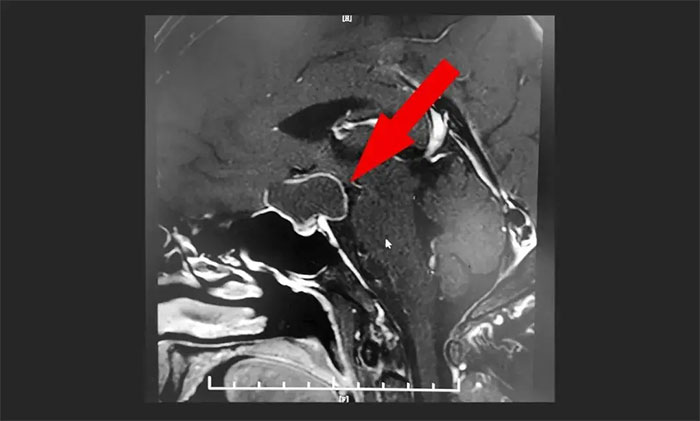

▲ MR显示鞍上区大囊样占位